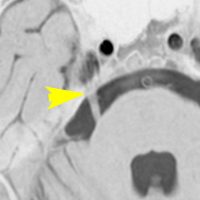

左側の写真は,顔面神経の根っこを前下小脳動脈が圧迫しているところです。矢印が示すのは,脳から顔面神経が出たところ(REZ レズ)です。ここが圧迫されないと顔面けいれんは起こりません。右側の写真は,動脈をよけて顔面神経のREZを解放したところです。長い間の圧迫でちょっとヘコんでいます。これが最も多いタイプです。